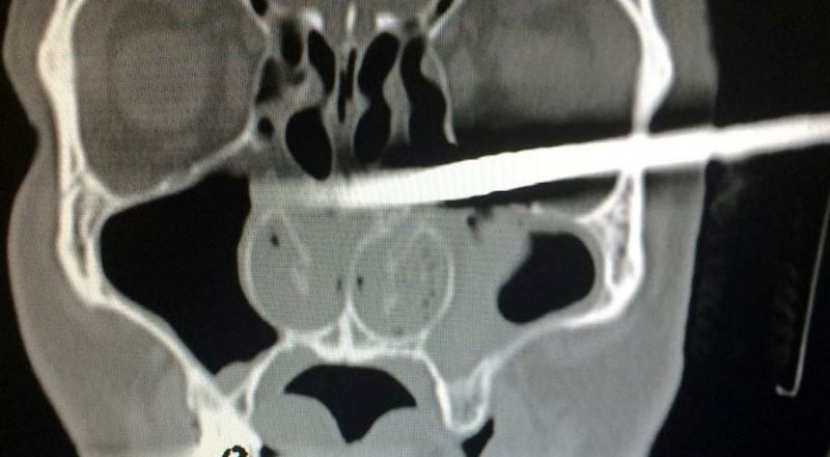

В Польше мужчина самостоятельно пришел в отделение «скорой помощи» с 38-сантиметровым деревянным колом в голове, пишет Tengrinews.kz со ссылкой на New York Post.

40-летний житель города Конин Камиль Подвински занимался ремонтом в своем доме, когда поскользнулся и напоролся на острый деревянный брусок. Тот словно копье пробил его череп насквозь. Кол вошел чуть ниже глазницы и вышел через затылок.

Врачам потребовалась помощь пожарных, которые обрезали кол, и мужчину смогли поместить в рентген-аппарат. Затем сохранявший спокойствие мужчина был переведен в специализированный госпиталь в Познани, где ему успешно удалили посторонний предмет. «Это чудо, что кол не попал в глаз и не причинил серьезных повреждений», - отметили в клинике.